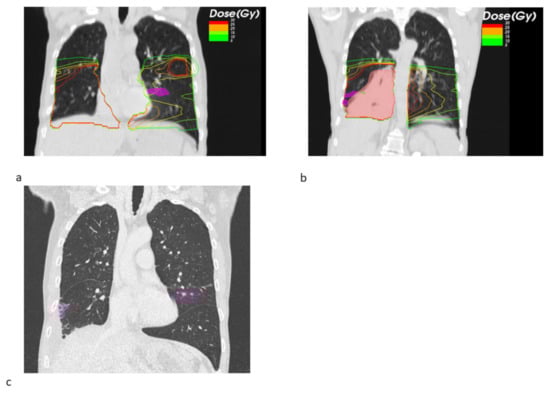

Figure 1. Transversal radiotherapy (RT) planning CT slices showing the EQD2 isodoses and pneumonitis contours (magenta) and GTV contours (light red) for a SBRT + ICB case (a) and for a SBRT case (b). Exemplary transversal slices from the follow up CT showing the pneumonitis and its contours (magenta) for the SBRT + ICB case (c) and the SBRT case (d).

Looking at the dosimetric results in more detail, we observed a trend towards a decreased fraction of the pneumonitis volume receiving a high dose of EQD2 > 20 Gy SBRT + ICB (22.26% vs. 71.14%, p = 0.549), whereas the mean low dose fraction with EQD2 < 10 Gy was numerically larger (39.02% vs. 26.99%). Figure 1 shows the pneumonitis extensions and EQD isodoses for two exemplary cases from both groups. For the depicted SBRT + ICB case, the pneumonitis affects both lungs with a rather small single-sided GTV distant from the resulting radiological changes. For another patient, who received SBRT with 45 Gy in 3 fractions to a small left-sided tumor, we also found bilateral extent of pneumonitis, as shown in Figure 2. This patient received additional SBRT for liver metastasis at the same time with the same dose fractionation regime; however, the extent of pneumonitis does not correlate with the dose distribution. For dosimetric analysis, we used sum doses to prevent overestimation of the effect attributed to the lung SBRT. A third patient also showed the bilateral extent of pneumonitis. This patient received hypofractionated, contralateral mediastinal RT with 45 Gy in 15 fractions a month prior to SBRT. Since the extent of the pneumonitis volume in the contralateral right lung is more likely caused by the irradiation of the right side, we considered only the pneumonitis contour from the left SBRT side for analysis. However, to not overestimate the dosimetric effect of SBRT alone, we used the sum EQD2, as shown in Figure 3a, for dosimetric evaluation as well.